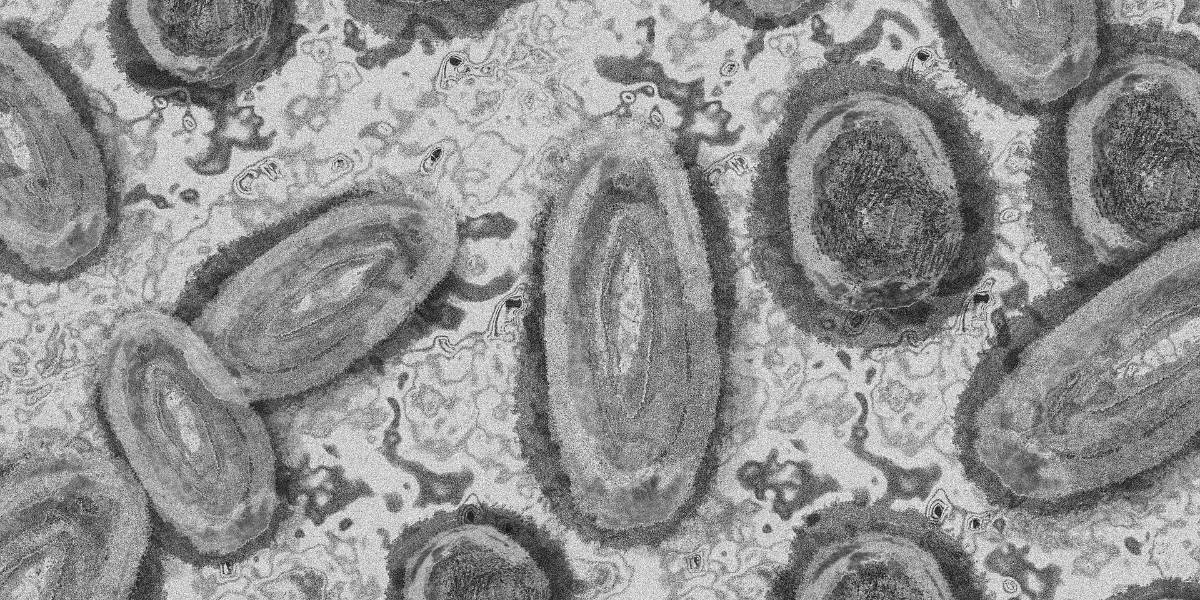

Viruela del mono: antivirales podrían reducir la duración de los síntomas

La viruela del mono, pariente cercano del virus de la viruela, es una enfermedad rara clasificada como enfermedad infecciosa por la Agencia de Seguridad Sanitaria del Reino Unido.